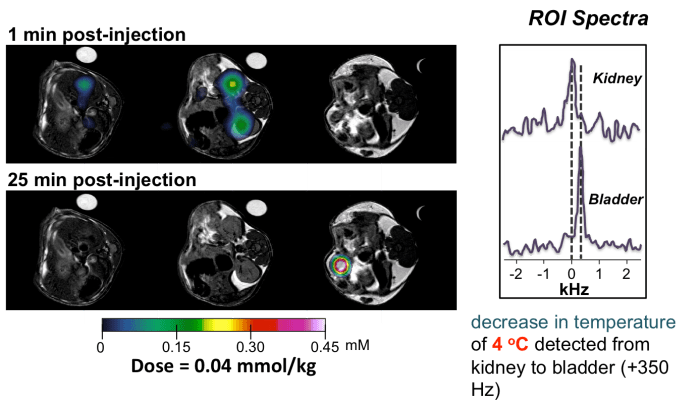

Following this MRI work I joined the group of Professor David Parker in Durham, and spent two years developing molecules for detection by MRI. We developed molecular probes, using lanthanide complexes, that are more sensitive than current contrast agents used in the clinic, and which can also act as ‘smart’ molecules to read out information in the body, such as tissue acidity and temperature.